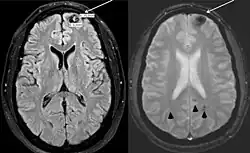

The person's largest cavernous malformation is shown in the left frontal pole. This lesion has classic signs of hemorrhage (white arrows). More lesions compatible with cavernous malformations in other areas of the brain can also be observed (arrowheads). Poland syndrome.[2]